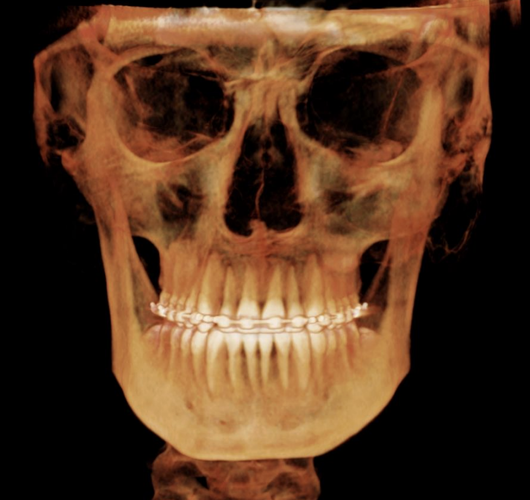

I slouched my way through my early teens and got fed fucking slop when i was a child. My maxilla is recessed and i convinced my parents to get a skull scan done for me, in hopes of getting MSE. I know that my ccw is cooked and i need to work on hella things. The doctor that did the scan said she can put in aligners to widen my upper palatte, idk if its cope or not, the main problem is that my ortho keeps ignoring my problem and just says my upper jaw looks fine. Ice made an appointment with a CMD and will go there in a few days, does anyone have any tips on what to tell them to possibly get MSE? You can see that my maxilla is recessed on the scan, Ive attached it below

TELL ME WHAT YOU THINK

I slouched my way through my early teens and got fed fucking slop when i was a child. My maxilla is recessed and i convinced my parents to get a skull scan done for me, in hopes of getting MSE. I know that my ccw is cooked and i need to work on hella things. The doctor that did the scan said she can put in aligners to widen my upper palatte, idk if its cope or not, the main problem is that my ortho keeps ignoring my problem and just says my upper jaw looks fine. Ice made an appointment with a CMD and will go there in a few days, does anyone have any tips on what to tell them to possibly get MSE? You can see that my maxilla is recessed on the scan, Ive attached it below

TELL ME WHAT YOU THINK